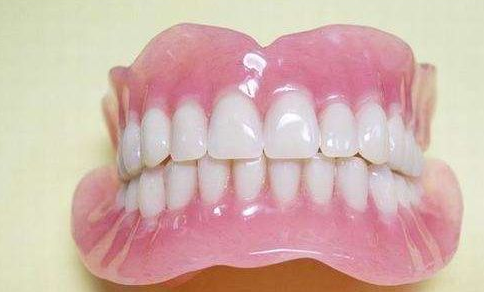

在牙齿修复领域,吸附性义齿和活动假牙是两种常见的修复方式。它们各自具有独特的特点和适用场景,了解它们之间的区别对于患者选择适合自己的修复方式至关重要。

首先,从固位方式来看,吸附性义齿和活动假牙存在显著差异。吸附性义齿通过利用大气压力,将义齿紧密地吸附在牙龈上。这种独特的吸附原理使得义齿在口腔中更加稳固,不易脱落。相比之下,活动假牙则主要依赖基托与黏膜的吸附力来固定,一旦牙龈结构发生变化,如牙龈萎缩或口腔黏膜变薄,活动假牙便容易松动甚至脱落。因此,从稳固性角度来看,吸附性义齿更具优势。

其次,在修复类型上,活动假牙具有更大的灵活性。它可以修复单颗、多颗、半口甚至全口牙齿缺失,适用范围广泛。而吸附性义齿则主要适用于半口和全口牙齿缺失的修复。如果患者只需要修复少数几颗牙齿,活动假牙可能是更好的选择;而如果患者面临的是半口或全口牙齿缺失,那么吸附性义齿可能更适合。

在舒适度与美观性方面,两者各有千秋。吸附性义齿在舒适度方面表现出色,由于其边缘封闭设计,减少了口腔黏膜的刺激,使得佩戴更加舒适。同时,吸附性义齿的颜色、形态等都能与天然牙齿相匹配,具有较高的美观性。而活动假牙虽然也能在一定程度上改善牙齿的外观和功能,但由于其固位方式的限制,可能在佩戴时会有一定的异物感。